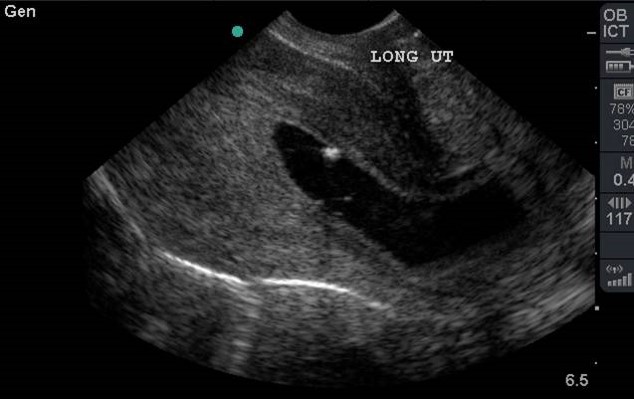

- Definitive evidence of an IUP is a gestational sac containing a yolk sac (YS) in two planes within the endometrium which usually occurs around 5-6 weeks gestational age.3,6 (Video 6 and 7)

- There is controversy with this definition; however, any earlier definition (eg, double decidual sign, empty gestational sac) is not accurate enough to ensure an IUP.7

- Prior to the develop of a YS, a gestation sac (GS) becomes visible in weeks 4-5.

- Be careful not to rely on a GS as an IUP, 10-20% of ectopic pregnancies have pseudo-gestational sacs.8 (Video 8)